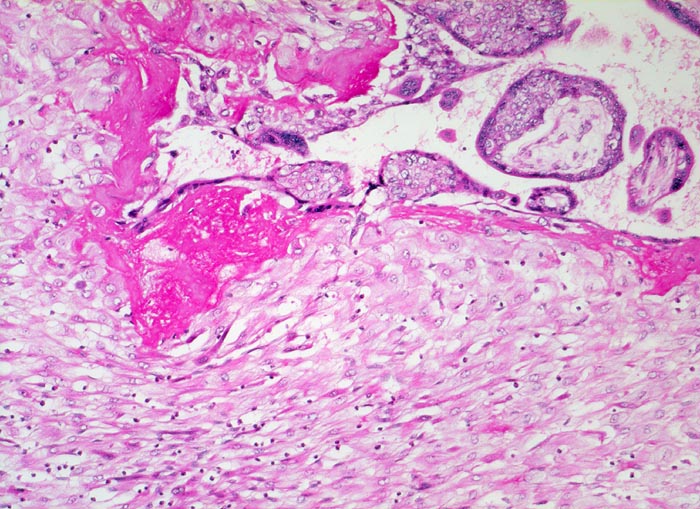

Morphologie:

• Plazenta accreta: Plazentarzotten haften dem Myometrium an ohne deziduale Zwischenschicht. Fibrin und Trophoblast kann vorhanden sein.

• Plazenta increta: Plazentaimplantation innerhalb des Myometriums.

• Plazenta percreta: Penetration der Plazentarzotten durch die gesamte Dicke des Myometriums hindurch.